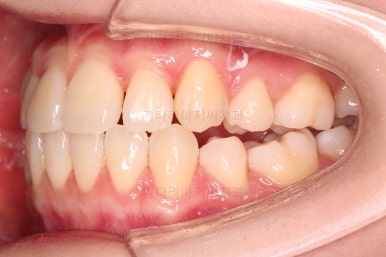

마찬가지로 초진 시 입안의 모습인데요.

전반적으로 약간 삐뚤지만 특히 윗니 앞니가 삐뚤고요.

송곳니는 덧니처럼 튀어나와 보이네요.

그리고 전반적으로 치아가 앞쪽으로 경사되어 있어서 앞니는 뻗친 느낌이 있네요.